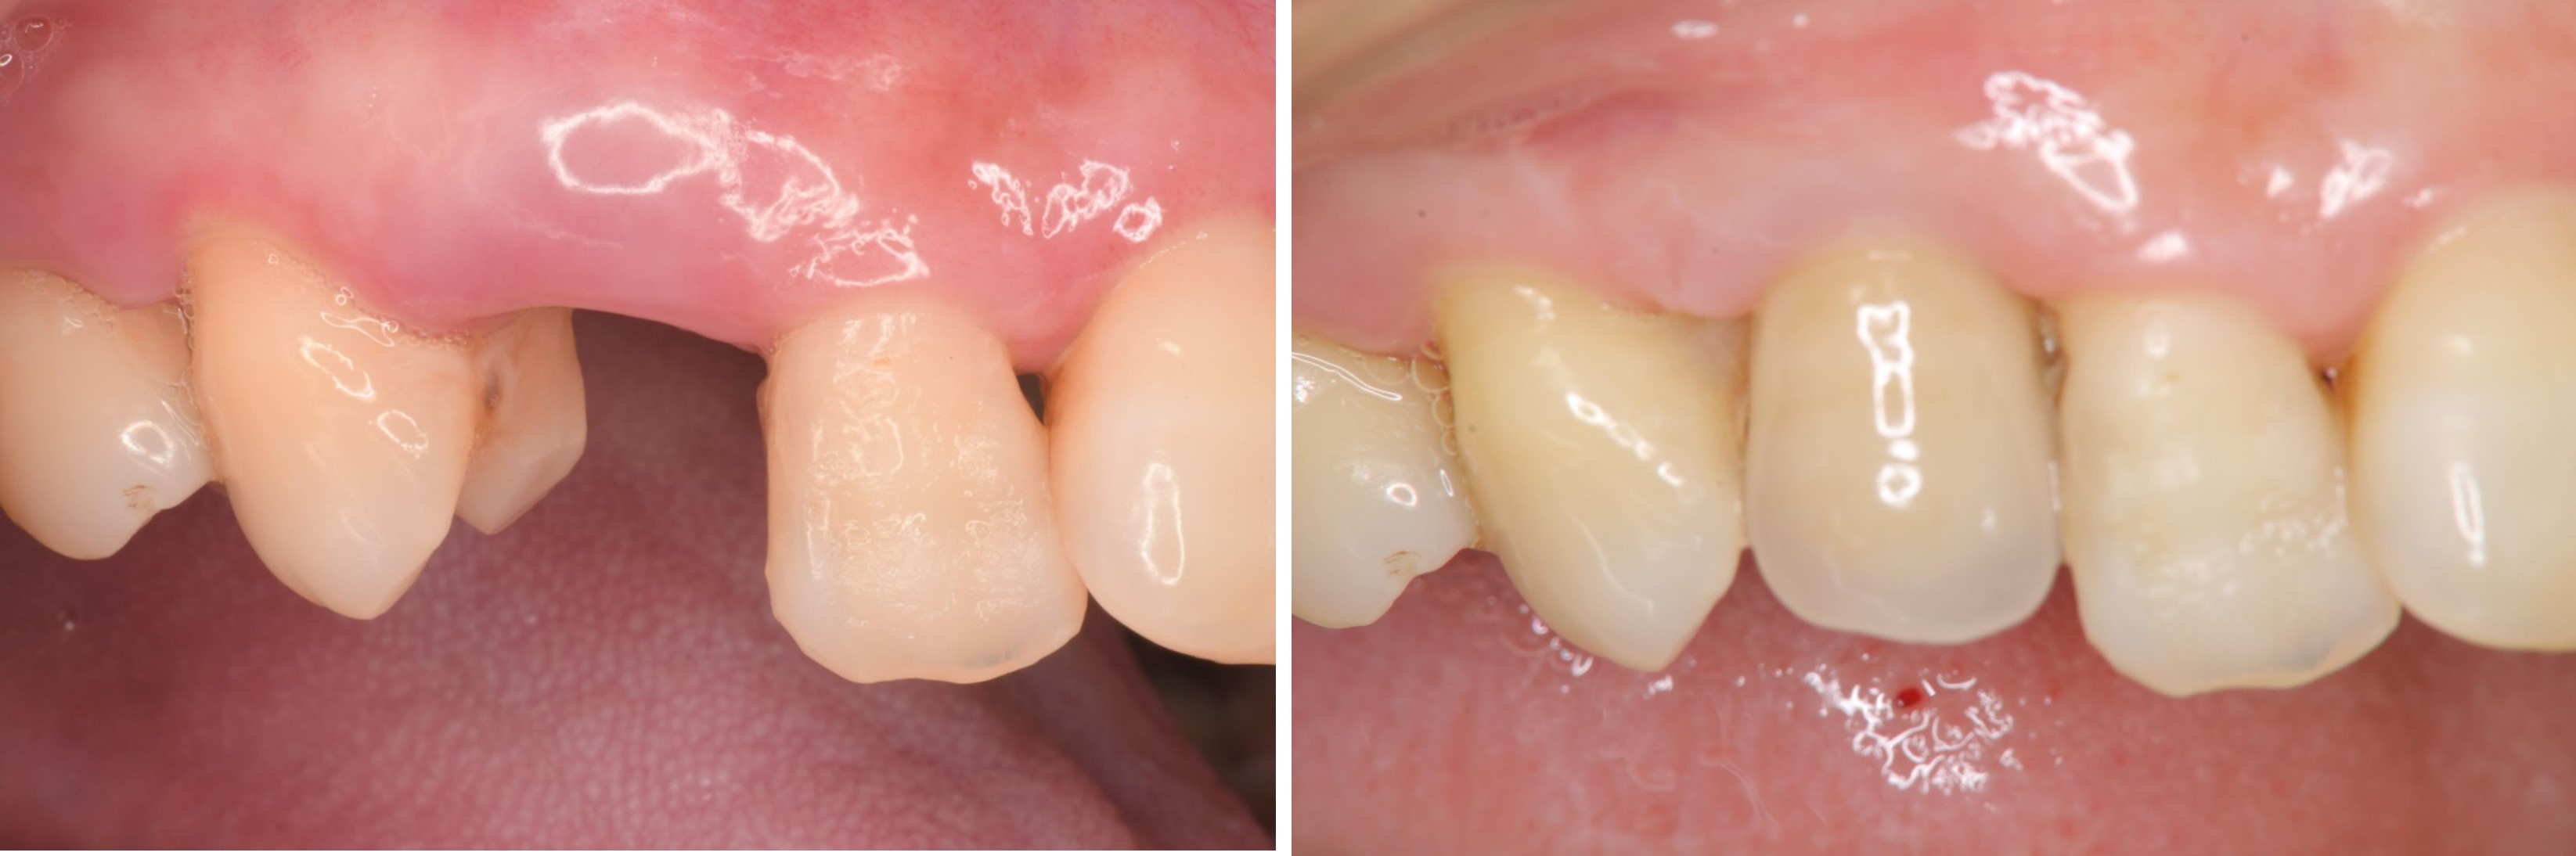

治療後,咬合牙周適應良好

治療後,密合度良好

術前、術後比較